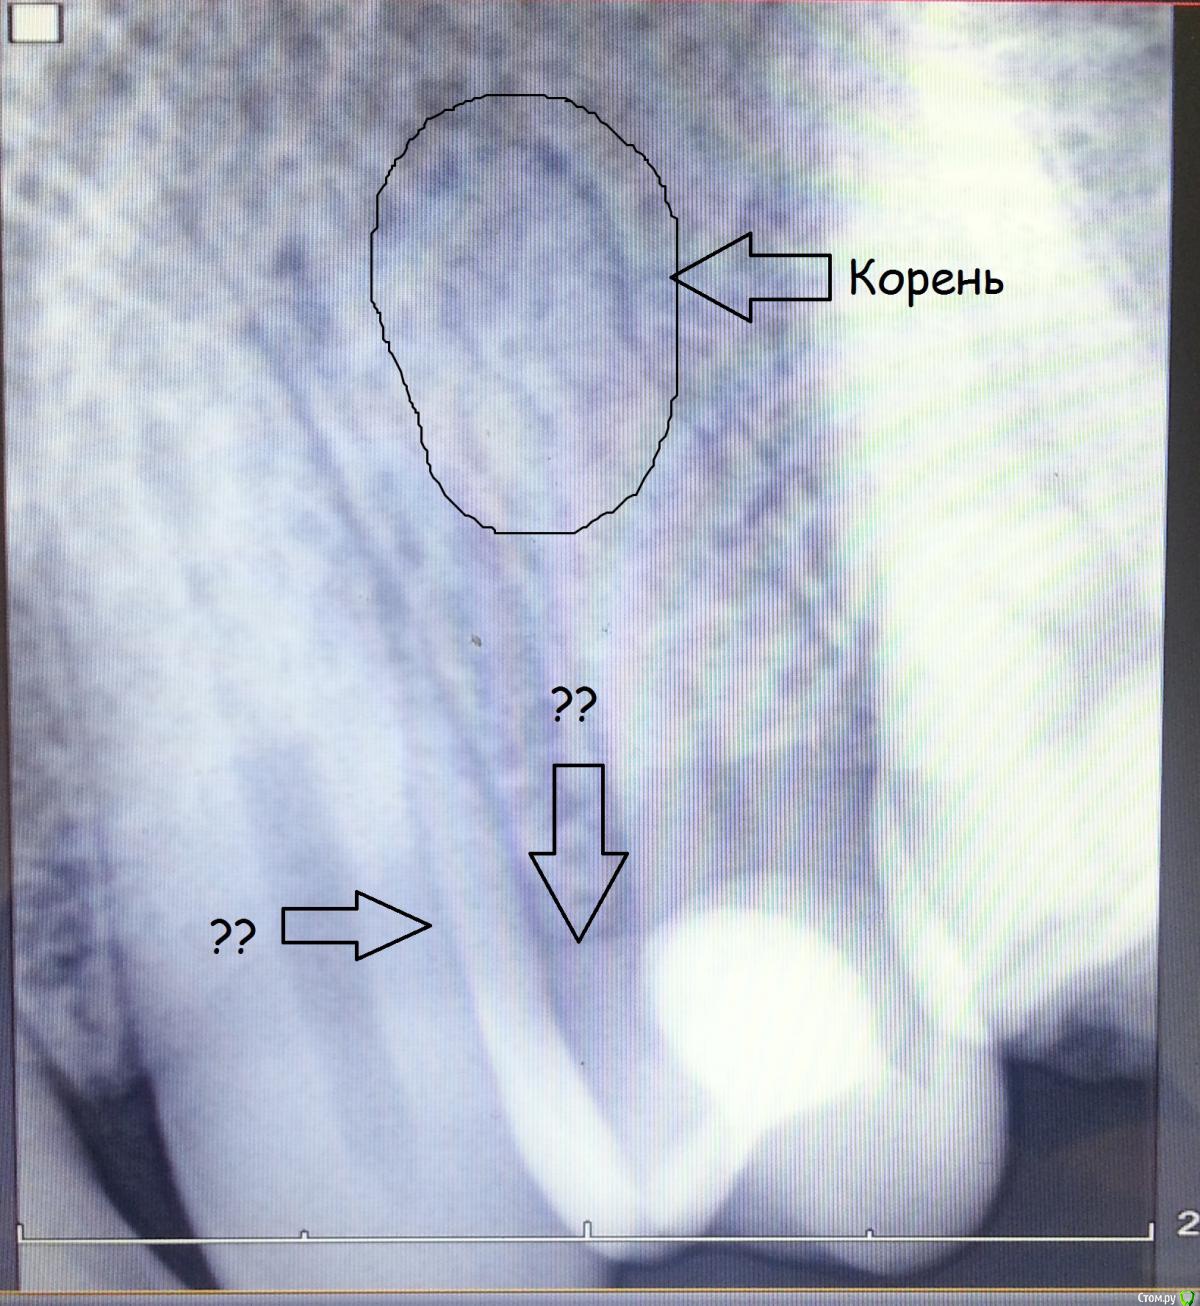

Sergdokrg25 Опубликовано 17 августа, 2015 Поделиться Опубликовано 17 августа, 2015 На ИРЗ есть всегда проекционное искажение и наложение соседних теней - здесь по вопросам сверзу вниз -1. зуб двухканальный с 2мя корнями у верхушки (это обведена одна из них) никакой патологии нет, 2. уровень десны с небной части зуба (проекционно удлинен), 3. эффект наложения двух соседних зубов (Да и в следующий раз делайте хотя бы скрин с экрана компьютера - больше сохраняется качество изображения) 1 Ссылка на комментарий

Nitrino1 Опубликовано 17 августа, 2015 Автор Поделиться Опубликовано 17 августа, 2015 На ИРЗ есть всегда проекционное искажение и наложение соседних теней - здесь по вопросам сверзу вниз -1. зуб двухканальный с 2мя корнями у верхушки (это обведена одна из них) никакой патологии нет, 2. уровень десны с небной части зуба (проекционно удлинен), 3. эффект наложения двух соседних зубов (Да и в следующий раз делайте хотя бы скрин с экрана компьютера - больше сохраняется качество изображения) Спасибо за отзыв,все понял, на счет скрина, я все это знаю, просто именно когда хотел эти изображения взять, прога заглючила, пришлось так снимать, ссори за качество Ссылка на комментарий